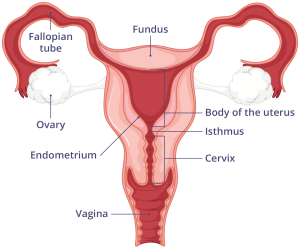

I.Ni ibihe bice by’umubiri w’umubyeyi bigira uruhare mu ibyara

Mu gikorwa cy’ibyara, hari imyanya myibarukiro igira uruhare rukomeye mu gutuma umwana avuka neza. Iyo myanya ni nyababyeyi, umuyoboro w’inda, n’uruhago, ndetse n’ibindi bice bifasha mu gutwara no gusohora umwana. Ibi bice byose bikorana mu buryo bwihariye kugira ngo ibyara bigende neza.

Nyuma y’ibi bice by’umubiri, hakenerwa kandi imisemburo y’ingenzi irimo oxytocin, estrogen, na progesterone. Iyi misemburo niyo ituma nyababyeyi ikomera cyangwa igororoka, igafasha mu gutangira no gukomeza imihango y’ibyara, bityo igikorwa cyose kikagenda mu buryo bwizewe.

Nyababyeyi (Uterus)

Ni igice gikomeye giherereye imbere mu nda, aho umwana aba ari mu mutekano mu gihe cyose umubyeyi atwite. Nyababyeyi iha intungamubiri n’umwuka binyuze mu ngobyi (placenta ) ikanamuha urwinyagamburiro rwo gukuriramo neza. Iyo igihe cyo kubyara kigeze, nyababyeyi ni yo isunika umwana kugira ngo avuke.

Inkondo y’umura (Cervix)

Ni igice gihuza nyababyeyi n’inzira y’umwana asohokeramo. Mu gihe cyo kubyara, inkondo y’umura igenda yaguka buhoro buhoro kugira ngo umwana abone aho anyura. Iyo itaguka neza, kubyara biragorana.

Inzira y’umwana asohokeramo (Vagina)

Ni inzira umwana anyuramo agiye kuvuka. Ni igice kigomba kuba cyoroshye kandi gifite imbaraga zo kwaguka kugira ngo umwana asohoke neza.

Ingobyi ( placenta)

Ni urutiriro rw’inda rufasha umwana kubona amaraso, intungamubiri, n’umwuka. Placenta ikunze kwifata ku rukuta rw’inyababyeyi (uterine wall), cyane cyane mu gice cyo hejuru cy’inyababyeyi (fundus) cyangwa inyuma (posterior wall). Aha ni ho haba amaraso menshi, bikayiha ubushobozi bwo guha umwana ibiryo n’umwuka.

Kuba placenta ikunze kwifata hejuru cyangwa inyuma bituma inzira y’umwana (inkondo y’umura) idahagarikwa, bityo kubyara bikagenda neza.

Imitsi y’amaras0 (uterine blood vessels)

Mu ibyara, imitsi y’amaraso igira uruhare mu gutanga oxygen n’ibindi bikenerwa ku myanya myibarukiro, ndetse no gufasha mu mikorere y’inyababyeyi. Iyo mitsi irimo:

– Imitsi mito (capillaries): niyo itanga amaraso ku bice byose bya nyababyeyi.

– Imitsi minini (arteries and veins): zifasha mu gutwara amaraso menshi, zigatanga imbaraga n’ibikenerwa mu gihe nyababyeyi ikora.

– Uterine arteries: imitsi itanga amaraso ku nyababyeyi, ikaba ingenzi cyane mu gihe cyo kubyara.

Imitsi y’amaraso rero ikorana n’imyanya myibarukiro kugira ngo ibyara rigende neza, ikanafasha mu kugabanya amaraso atakara cyane nyuma yo kubyara.